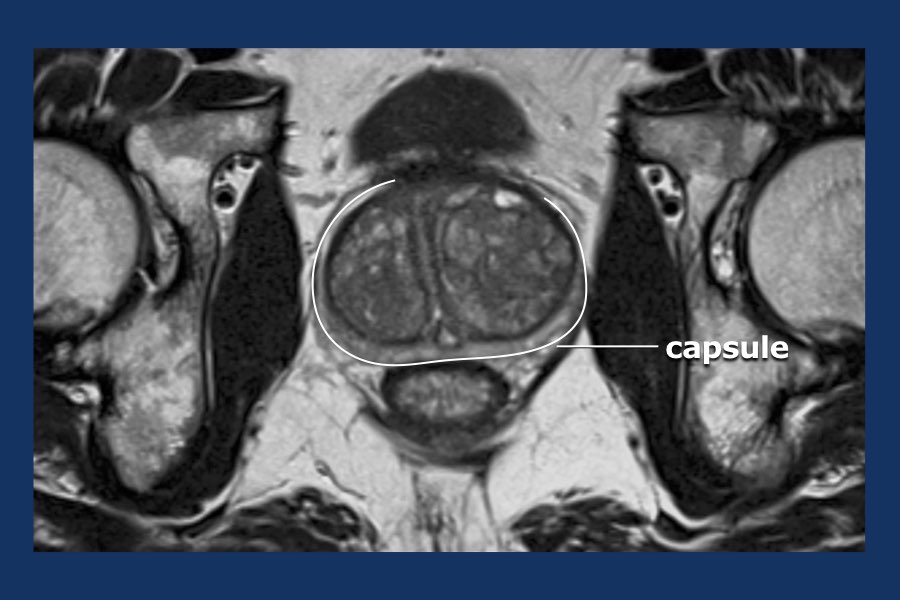

From radiologyassistant.nl

The Radiology Assistant Prostate Cancer PIRADS v2 Define Pi Rads the european society of urogenital radiology (esur) in 2012 established the prostate imaging—reporting and data. to improve early diagnosis and treatment of prostate cancer, acr, admetech foundation and esur formed a joint effort to develop. Define Pi Rads.